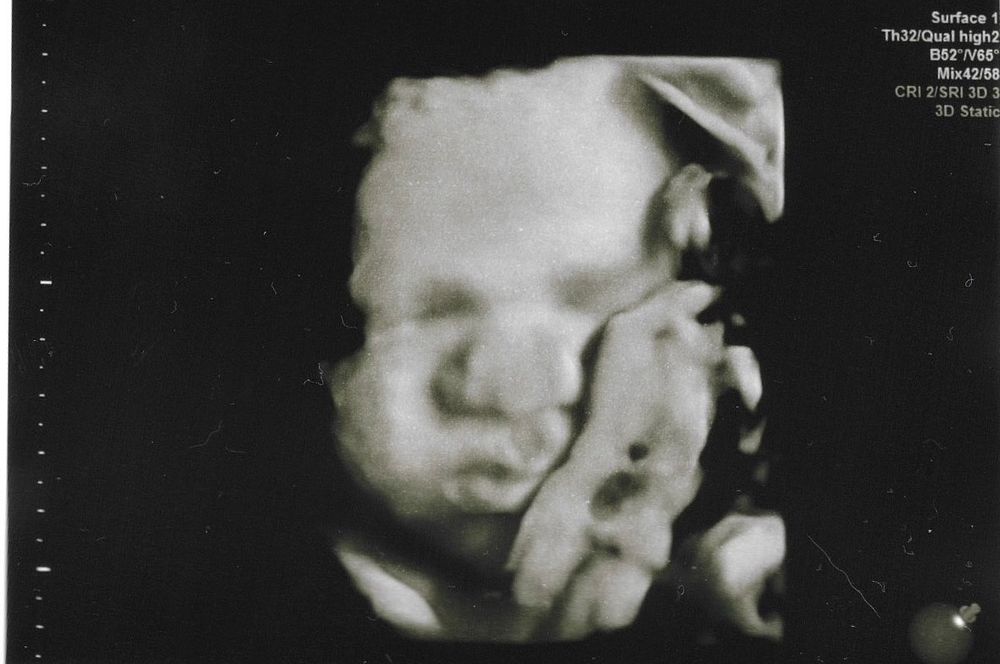

33,2 УЗИ 3D

Мой ВикторУЗИ 33,2 (по фетометрии 33,0)

Дитёныш весьма милый, опять сосал кисть, из-за чего как бы она не пыталась выцепить хорошее фото с четкими чертами лица, не получалось. Хотя она особо и не пыталась, даже ни разу меня не повернула. Хотя на прошлом вертела долго. Ну и такие фото тоже весьма себе хорошие.